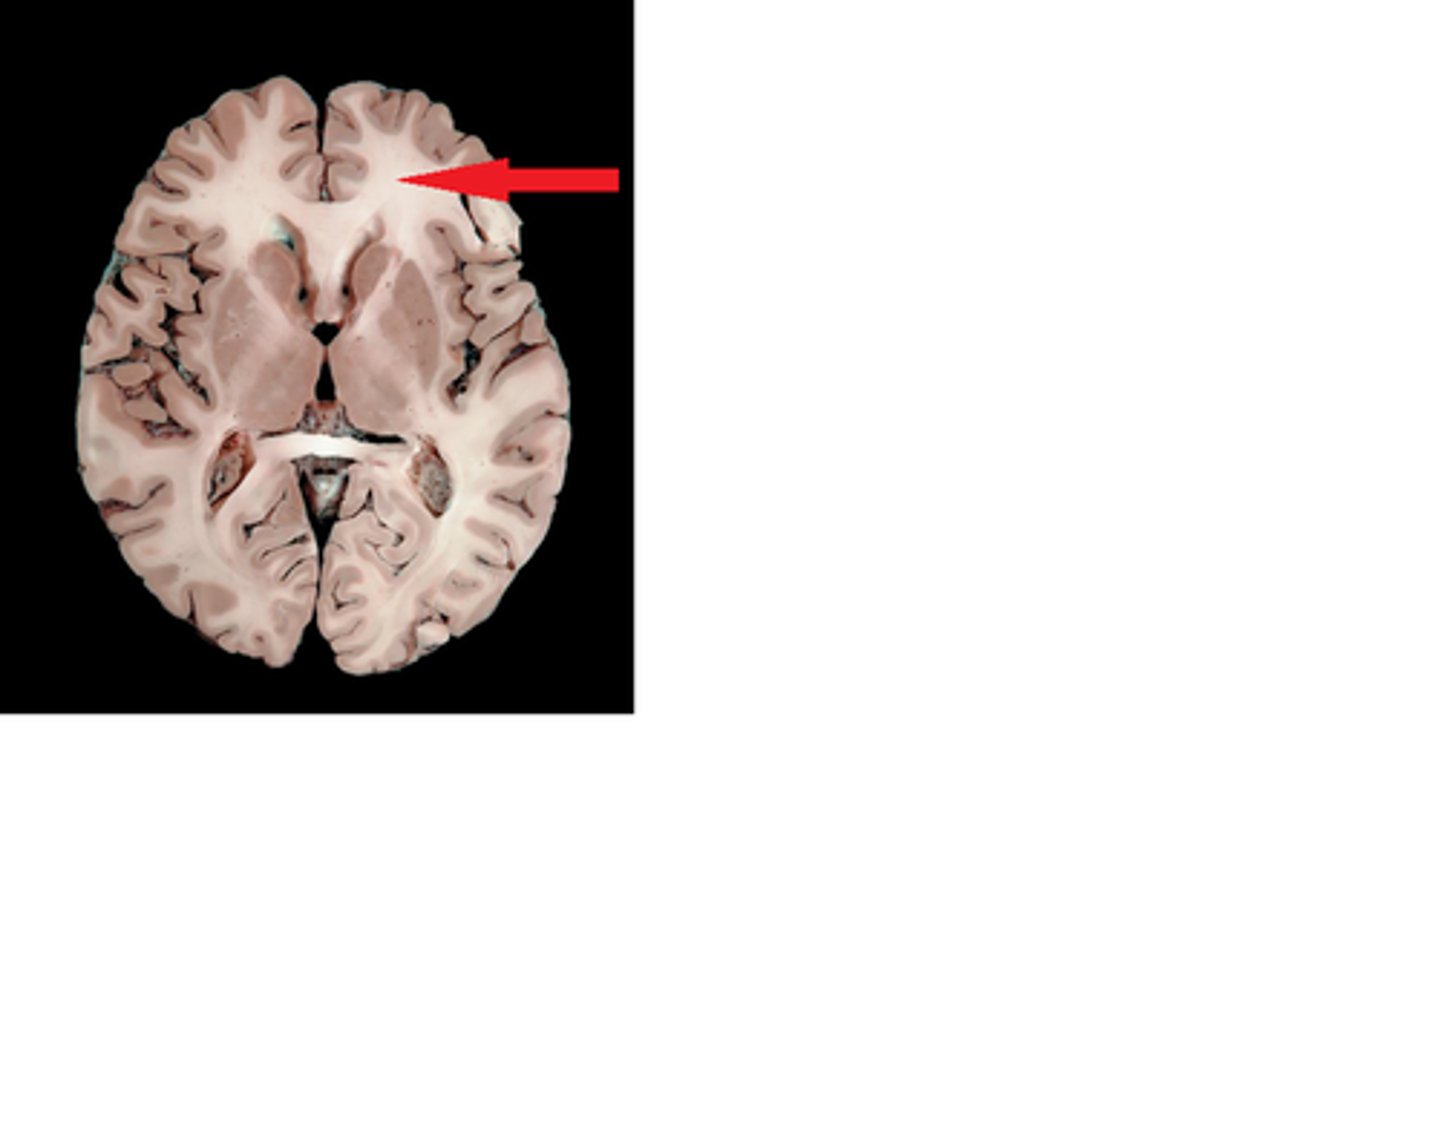

Right Lateral Ventricle

Interventricular Foramen

third ventricle